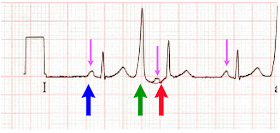

81-летняя женщина с анамнезом терминальной стадией болезни почек, а также гемодиализом, нормальным радионуклидным стресс-тестом годом ранее, малоинвазивной замены аортального клапана и приемом варфарина, фибрилляцией предсердий, диастолической сердечной недостаточностью, ожирением, диабетом, гипертонией и инсультом были доставлены в отделение неотложной помощи по поводу нарушений психики и гипотонии, которые начались ближе к концу сеанса диализа. По прибытии скорой помощи в ее диализный центр специалистам не удалось измерить артериальное давление. Была записана догоспитальная ЭКГ, которая выглядела идентичной исходной ЭКГ при поступлении, показанной ниже, и врач скорой, обеспокоенный состоянием пациентки и ее ЭКГ, позвонил врачу клиники и спросил, следует ли планировать экстренную катетеризацию:

Что бы вы сказали?

Интерпретация ЭКГ

- Синусовый ритм, АВ-блокада 1-й степени, частые предсердные или узловые экстрасистолы (вызывающие несколько периодов регулярно нерегулярного ритма)

- Длительность QRS составляет приблизительно 0,1 с, с морфологией, предполагающей блокаду передней ветви.

- Диффузная депрессия ST, максимальная в V4-V6 и отведении II, с обязательной реципрокной элевацией ST в aVR

Впечатление

Находки согласуются с диффузным несоответствием потребности и доставки без признаков фокальной окклюзии. Как мы много раз объясняли в этом блоге, дифференциальный список при такой картине ЭКГ огромен и включает неокклюзионный ОКС (например, острый левый главный ОКС, болезнь трех сосудов с неокклюзионной причиной) или любую причину, не относящуюся к ОКС, любая из причин (или вместе) снижающие доставку или увеличивающие потребность. Список причин для этой последней возможности слишком длинный, чтобы перечислять его снова, но общие причины включают гипотонию, гипоксемию, сепсис, желудочно-кишечные кровотечения и т. д.